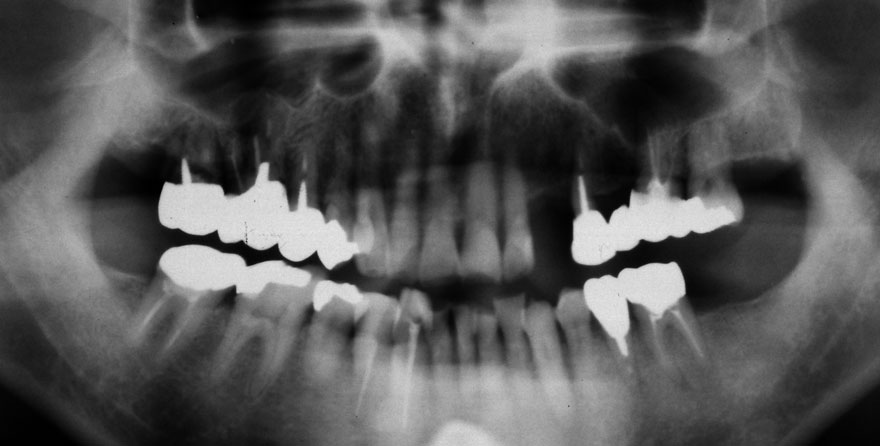

初診時 40歳 女性 平均歯槽骨喪失量:3.14mm

河田歯科医院

32年後 72歳

平均歯槽骨喪失量:3.22mm

32年間喪失量:-0.08mm

年間喪失速度:-0.002mm

(ケア頻度:1.86ヵ月ごと)